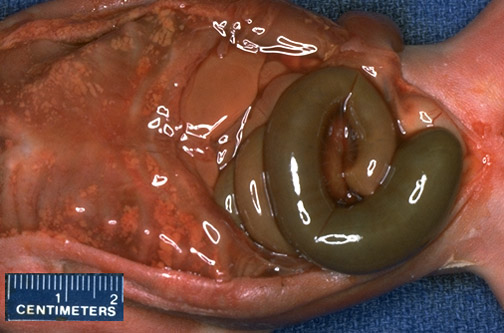

| The meconium-filled bowel ends in a blind pouch. This is atresia of the bowel. Such a defect, like many anomalies, often happens along with other anomalies. Bowel atresias are accompanied by polyhydramnios, since the swallowing and absorption of amniotic fluid by the fetus is impaired. |